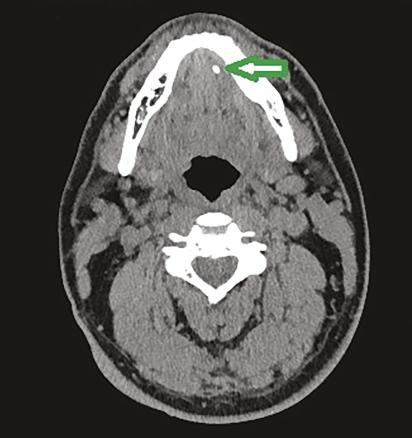

Scanner montrant un calcul du tiers antérieur du canal de Wharton gauche.

Extrait de : Pathologies lithiasiques des glandes salivaires